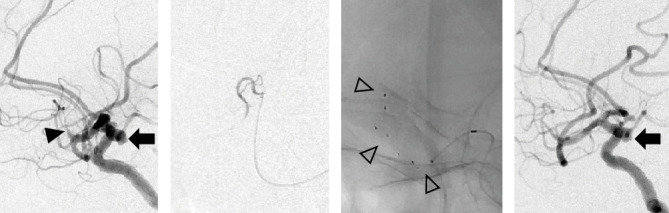

目的:随着机械取栓术(MT)在大血管闭塞性卒中中的应用越来越普遍,在MT靶血管中发现未破裂脑动脉瘤(uANs)的情况越来越多,需要通过病例积累来建立此类病例的MT安全指南。在这项研究中,我们的目的是回顾和报告我院与MT靶血管相关的uAN病例。方法:在2018年1月至2021年12月期间,我院320例大血管闭塞性卒中患者中,我们选择了在MT靶血管中有uAN的患者,并分析了各种参数,包括闭塞的血管、uAN位置、uAN发现时间、血栓取出程序、材料、再通结果和uAN破裂发生率。结果:320例患者中,7例发生靶血管动脉瘤(2.2%)。其中4例在器械穿过闭塞病变(病变交叉(LC))之前识别出病变,3例在LC或再通后识别出病变。在回顾性回顾中,3例中有1例在术前计算机断层扫描中怀疑有uAN。取栓程序包括1例患者单独直接抽吸首次通过技术(ADAPT), 2例患者单独支架置入术(SR), 3例患者联合治疗,1例患者SR联合尿激酶局部输注。有效再通率(定义为TICI 2b或3)为57.1%(4/7)。平均穿刺到再通时间为77.4分钟,没有一例与MT相关的uAN破裂。结论:我们报道了7例MT靶血管中的uAN。虽然我们采用了与常规MT相同的策略和技术,优先考虑再通,但没有uAN破裂与MT相关。术前图像评估更重要的是考虑到在MT靶血管中存在uAN的可能性,以及根据每个患者的情况仔细选择MT程序。

Objective: With the increasing prevalence of mechanical thrombectomy (MT) for large vessel occlusion strokes, encountering unruptured cerebral aneurysms (uANs) in MT target vessels has become more common, necessitating case accumulation to establish safety guidelines for MT in such cases. In this study, we aimed to review and present cases of uAN associated with MT target vessels at our hospital. Methods: Among 320 patients who underwent MT for large vessel occlusion strokes at our hospital between January 2018 and December 2021, we selected patients with uAN in the MT target vessel and analyzed various parameters including the occluded vessel, uAN location, timing of uAN discovery, thrombus retrieval procedures, materials, recanalization outcomes, and uAN rupture incidence. Results: Of the 320 patients, 7 had aneurysms in the target vessel (2.2%). The uANs were identified before the device crossed the occluded lesion (lesion crossing (LC)) in four cases, while in three cases, identification occurred after LC or recanalization. In 1 of the 3 cases, a uAN was suspected on preoperative computed tomography at the retrospective review. The thrombectomy procedures included a direct aspiration first pass technique (ADAPT) alone in one patient, stent retrieval (SR) alone in two patients, combination therapy in three patients, and SR combined with local infusion of urokinase in one patient. The effective recanalization rate, defined as TICI 2b or 3, was 57.1% (4/7). The average puncture-to-recanalization time was 77.4 min, and there were no instances of uAN rupture associated with MT. Conclusions: We presented seven cases of uAN in the MT target vessel. No uAN rupture was associated with MT, although the same strategies and techniques of routine MT at our hospital were employed, prioritizing recanalization. Preoperative image assessment considering the possibility of a uAN being present in the MT target vessel is more essential, as well as careful selection of MT procedures according to the situation of each patient.